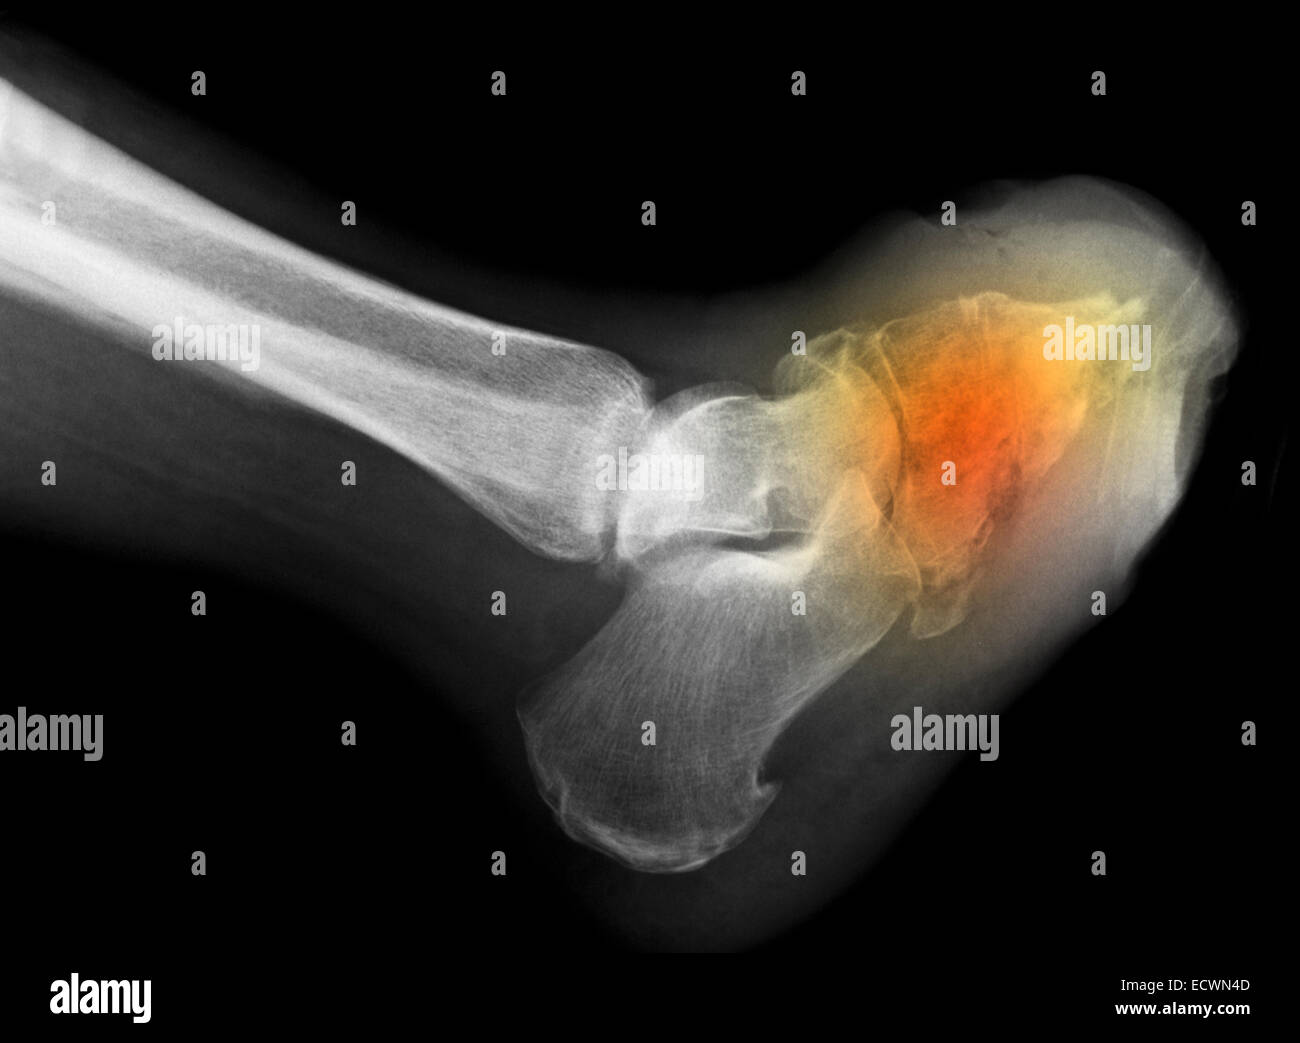

Infección en el hueso. Radiografía del pie de un paciente diabético

Xray mostrando la osteomielitis en el pie en una mujer diabética Pie Diabetico Osteomielitis Diabetic foot infections (dfis) typically begin in a. La amputación del pie o de la pierna se produce fundamentalmente por eventos relacionados con la isquemia o la infección, siendo esta última la causa principal 4. En la presente revisión se. Destruction of the base of 5th. La consecuencia más grave es la amputación 1. Diabetic foot osteomyelitis (dfo) is the. Pie Diabetico Osteomielitis.

Infección en el hueso. Radiografía del pie de un paciente diabético Pie Diabetico Osteomielitis Diabetic foot infections (dfis) typically begin in a. La consecuencia más grave es la amputación 1. Foot infections are a common and serious problem in persons with diabetes. Destruction of the base of 5th. La amputación del pie o de la pierna se produce fundamentalmente por eventos relacionados con la isquemia o la infección, siendo esta última la causa principal. Pie Diabetico Osteomielitis.